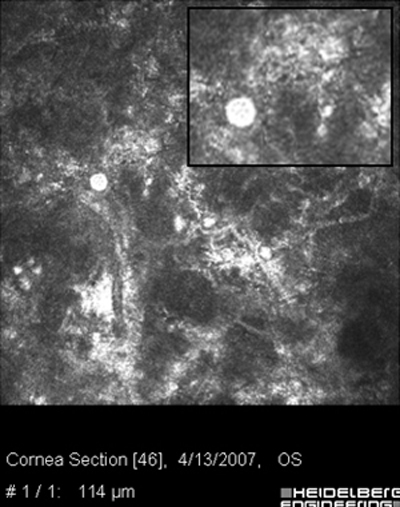

Ante la sospecha por los antecedentes e imágenes biomicroscópicas de una queratitis por Acantamoeba, debe hacerse su confirmación diagnóstica mediante extendidos de la superficie corneal para estudio microscópico, con las imágenes obtenidas “in vivo” con microscopía confocal (Figura 31 y 32) y mediante cultivos del parásito.

Fig. 31 Microscopía Confocal

Fig. 32 Comparar con quiste Acanthamoeba Fig 39

La positividad por la presencia de Acanthamoebas en uno o más estos estudios, asociada a las imágenes clínicas, confirma la etiología de la queratitis e indican la conducta terapéutica a seguir.